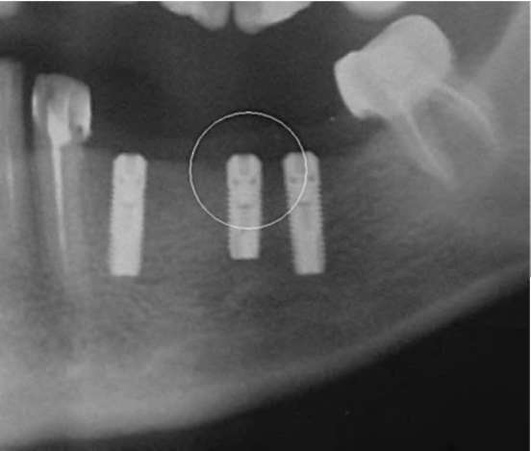

На рентгенограмме боковой проекции нижней челюсти при хроническом процессе характерна резорбция кости чаще в виде широкой щели у шейки зуба и по ходу корня, нередко в виде полулуния (рис. 14-18).

image

Рис. 14-18. Рентгенологическая картина ретенции зуба мудрости с полулунным очагом деструкции кости в проекции коронки